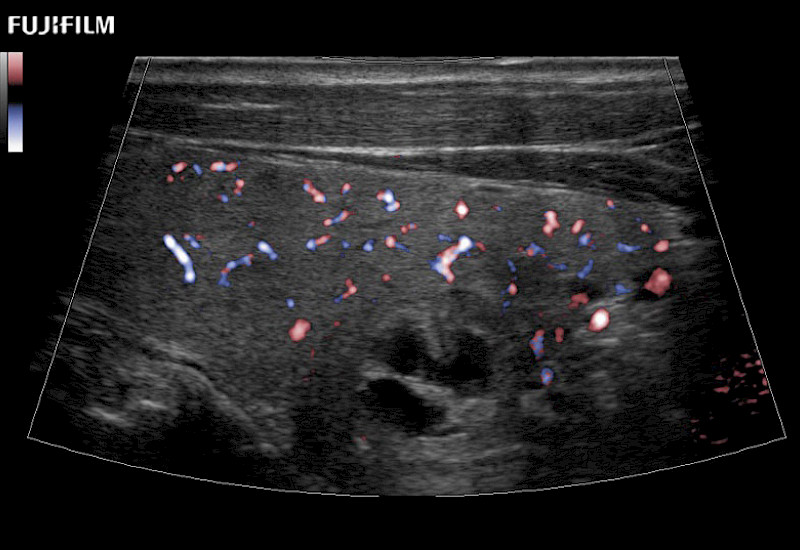

Fujifilm Healthcare understands that Surgical Oncologists demand excellence in their operating rooms — from their staff and the equipment they depend on. Fujifilm Healthcare's dedication to Surgical Oncologists provides outstanding ultrasound technology, professional support and the specialized tools necessary to best perform comprehensive real-time ultrasound imaging.

Our dedication to Surgical Oncology allows us to offer superior image quality, outstanding system reliability and intuitive use of cutting edge technology.